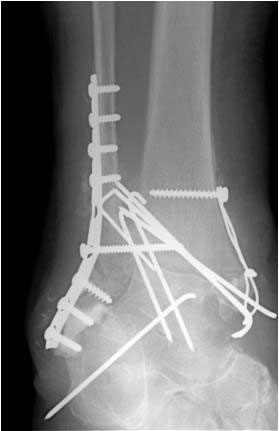

• Primäre oder posttraumatische Arthrose des OSG und USG (Abbildung 1, Abbildung 2).

• Revision einer gescheiterten Fusion des OSG/ USG (Abbildung 3, Abbildung 4).

• Pseudarthrosen (Abbildung 5, Abbildung 6).